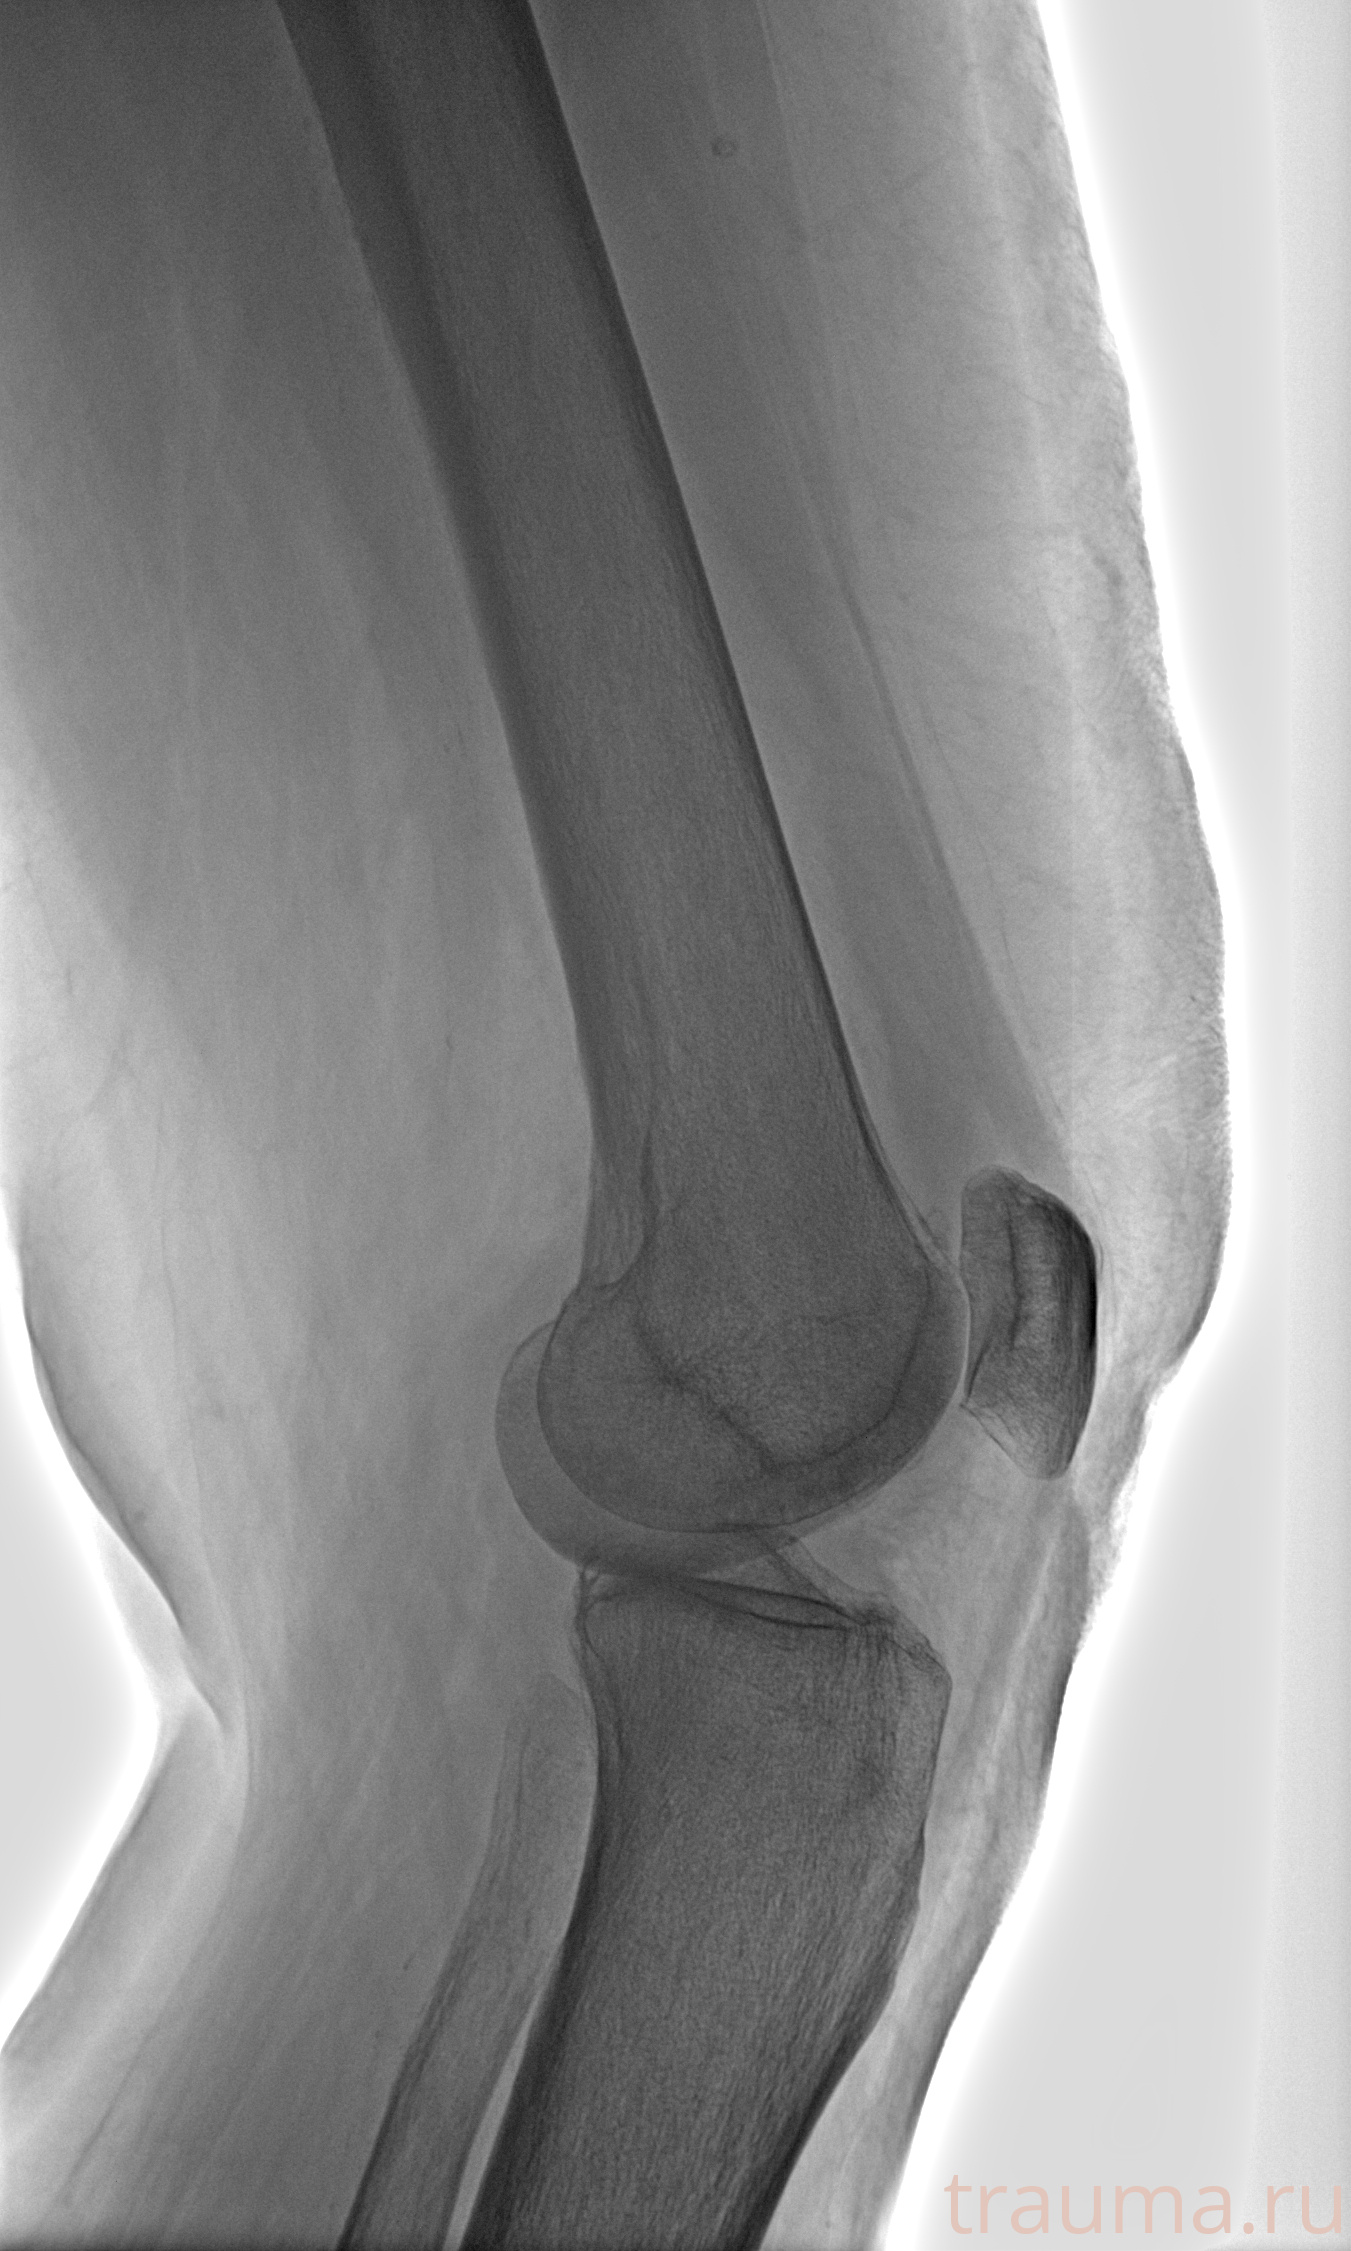

Рентген на дому: по вашему адресу приезжает врач-рентгенолог, травматолог-ортопед с мобильным рентгеновским аппаратом, проводит диагностику травмы или заболевания, делает необходимые рентгенограммы, дает рекомендации по дальнейшему лечению. Получить качественные снимки в домашних условиях возможно благодаря уникальной методике, разработанной МосРентген Центром для института  Склифосовского